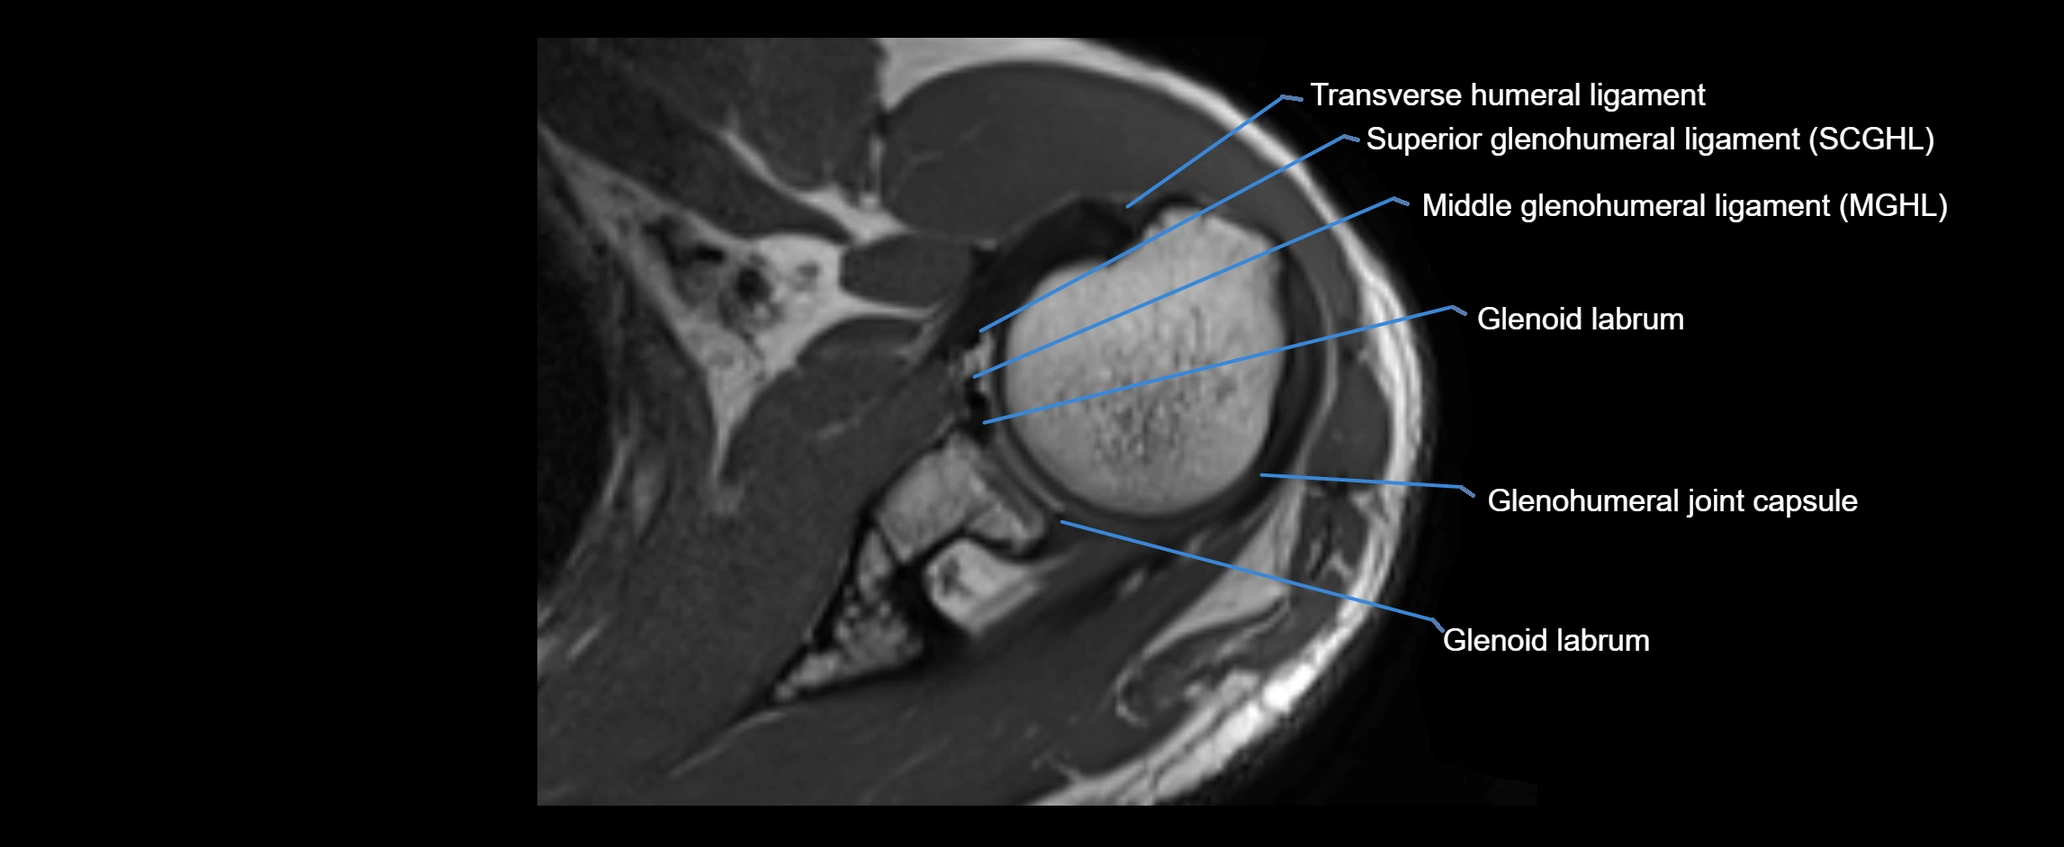

MRI images

image